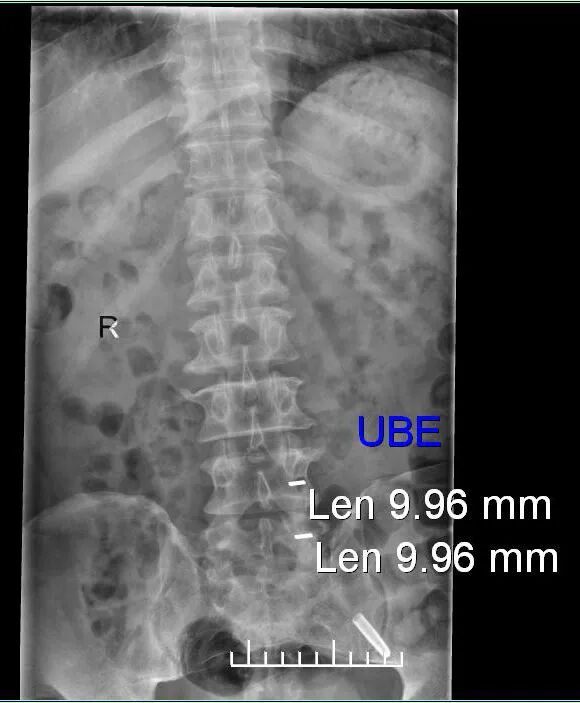

图4:术前定位影像

图5:术前定位影像